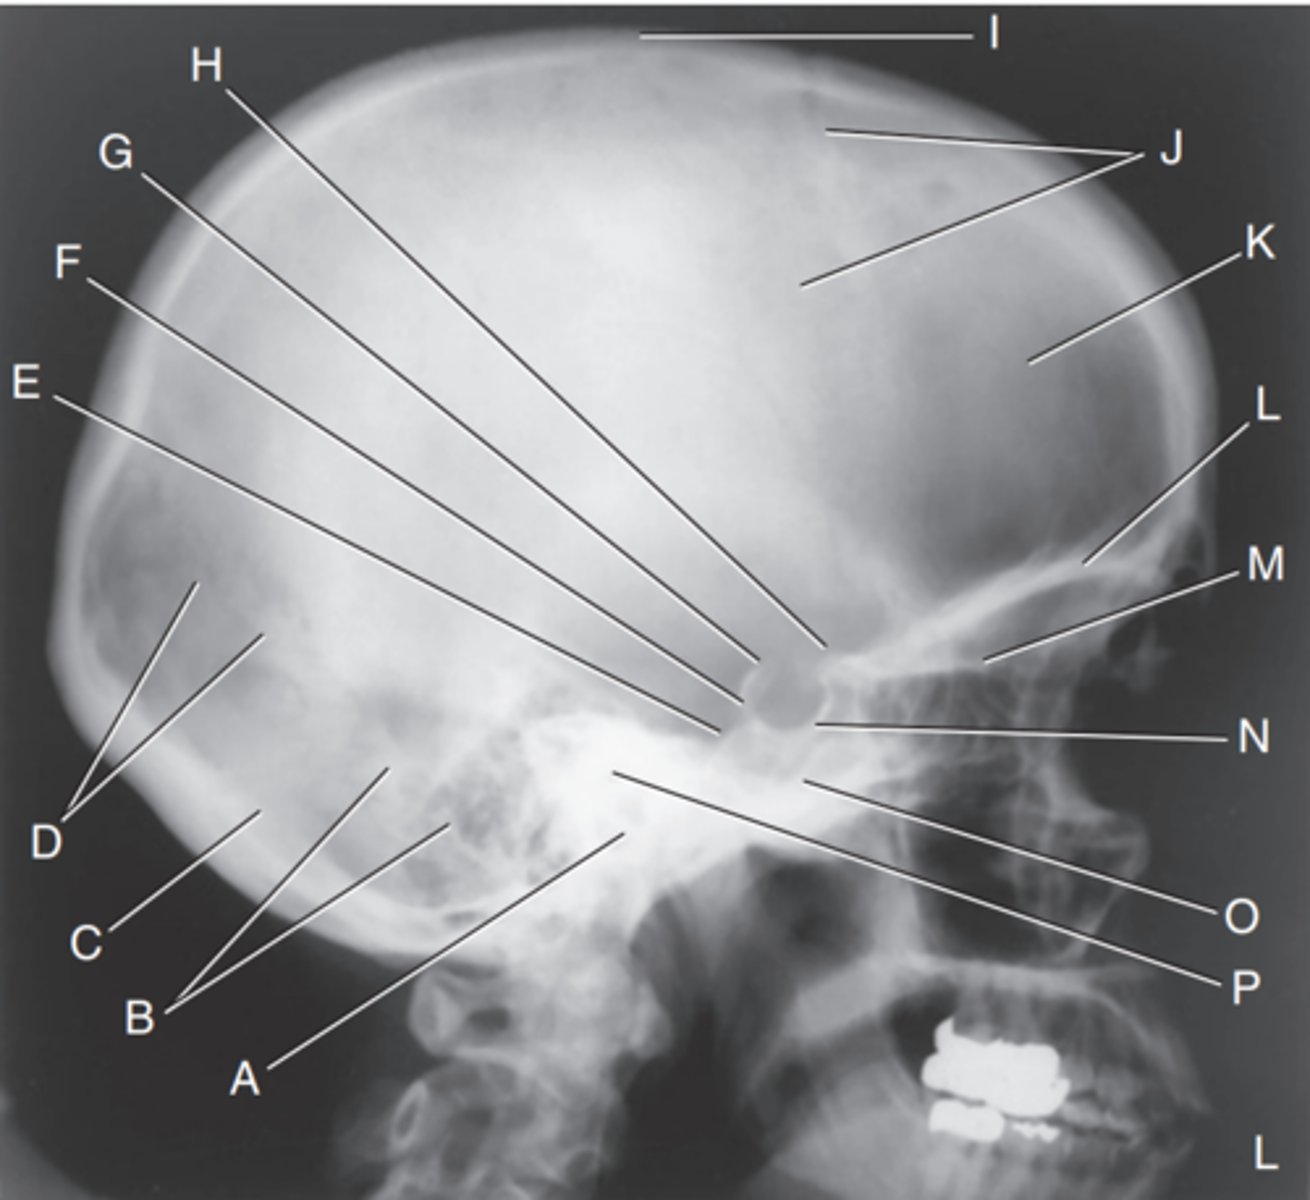

EAM

Label A

Mastoid portion of temporal bone

Label B

Occipital bone

Label C

Lambdoidal suture

Label D

Clivus

Label E

Dorsum sellae

Label F

Posterior clinoid processes

Label G

Anterior clinoid processes

Label H

Vertex of cranium

Label I

Coronal suture

Label J

Frontal bone

Label K

Orbital plates

label L

Cribriform plate

Label M

Sella turcica

Label N

Body of sphenoid (sphenoid sinus)

Label O

Petrous portion of temporal bone

Label P